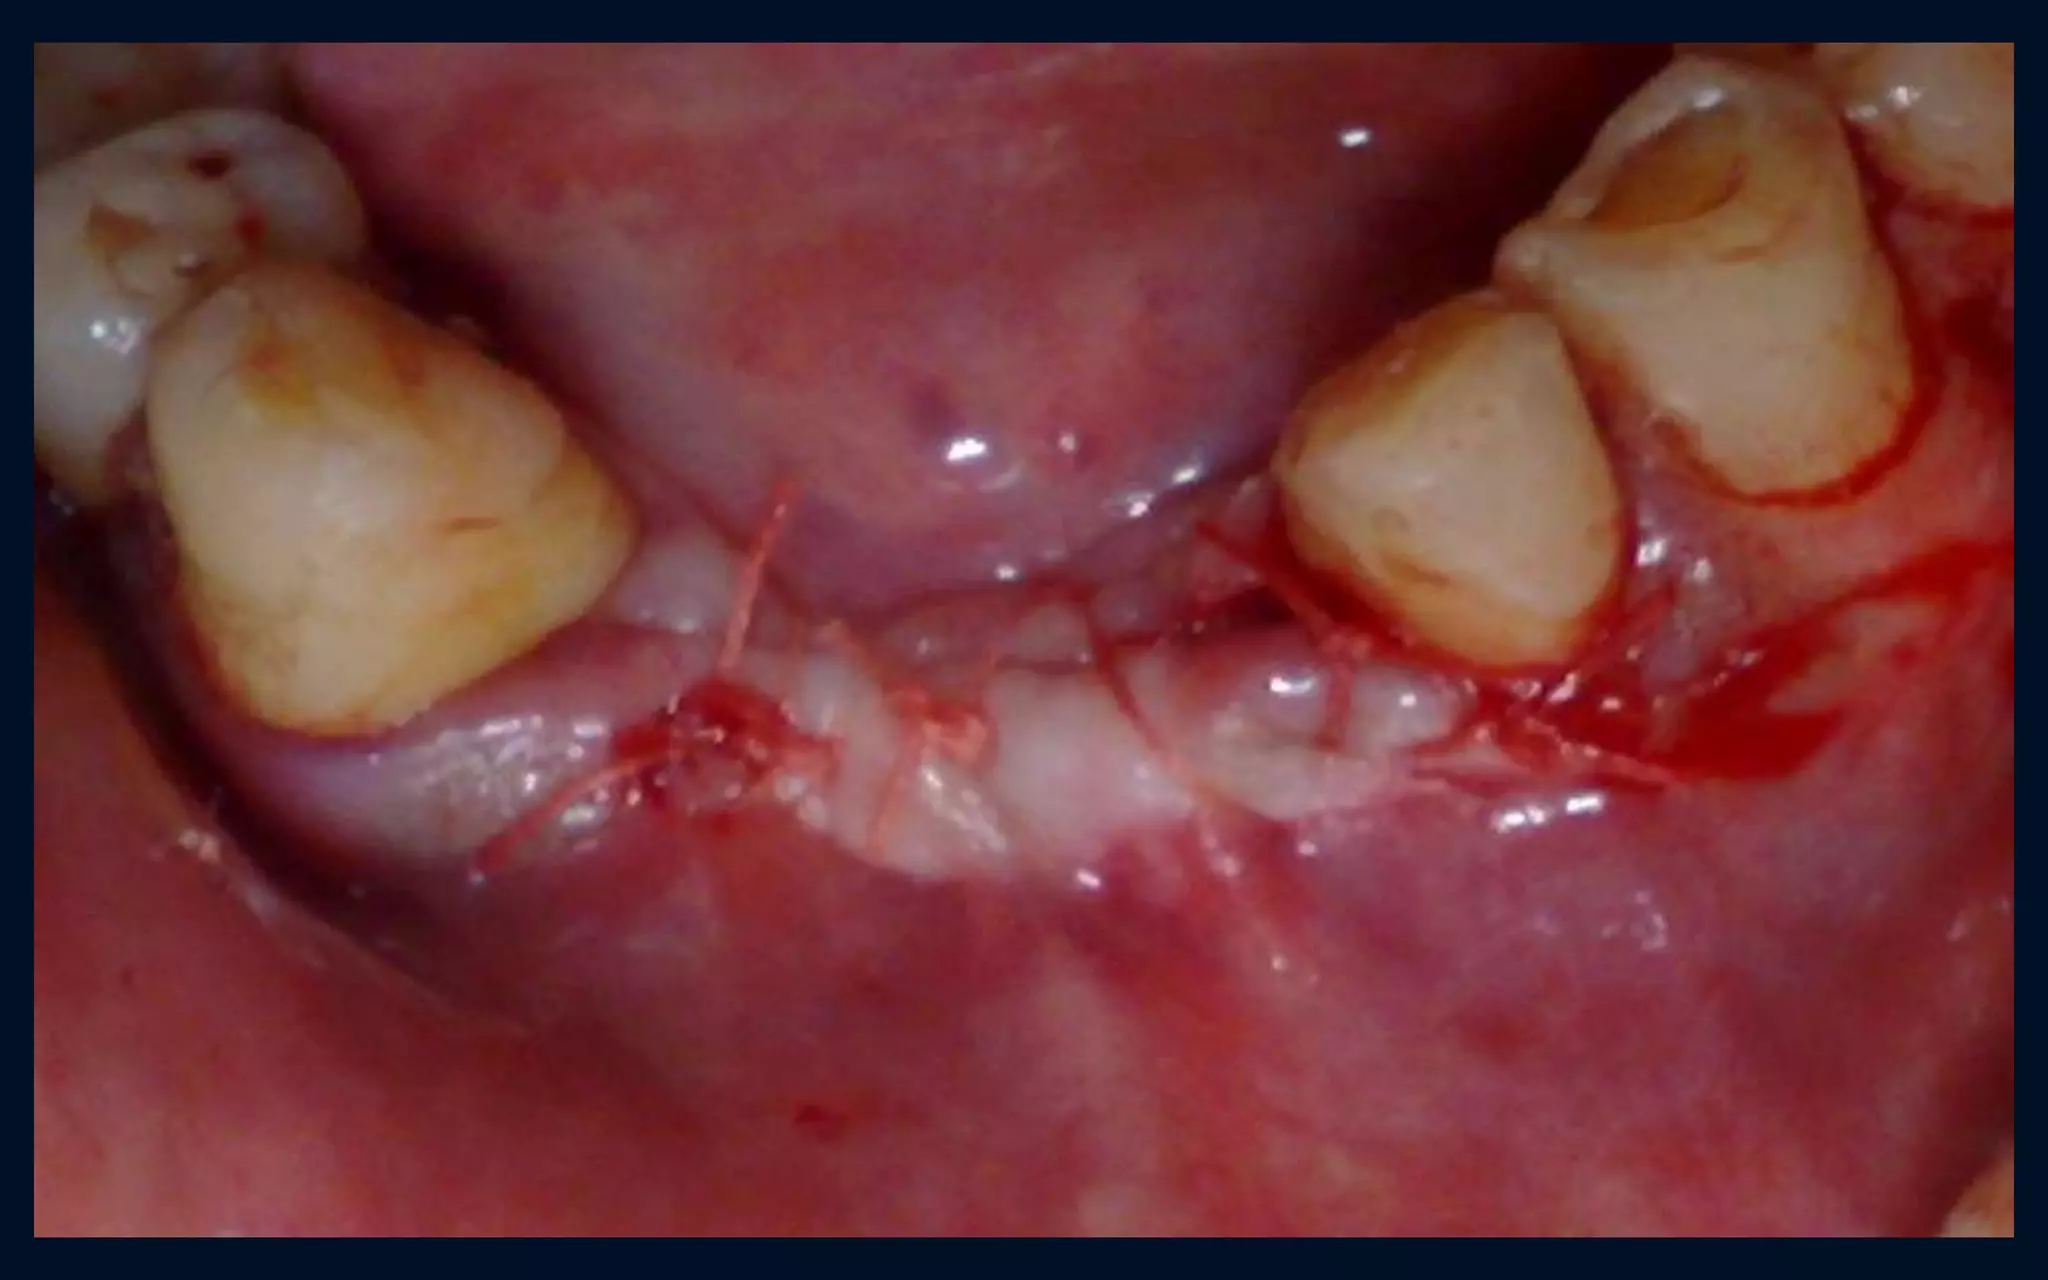

Crestal incision with releasing incisions

overdenture

P0ST-OPERATIVE….DAY - 2